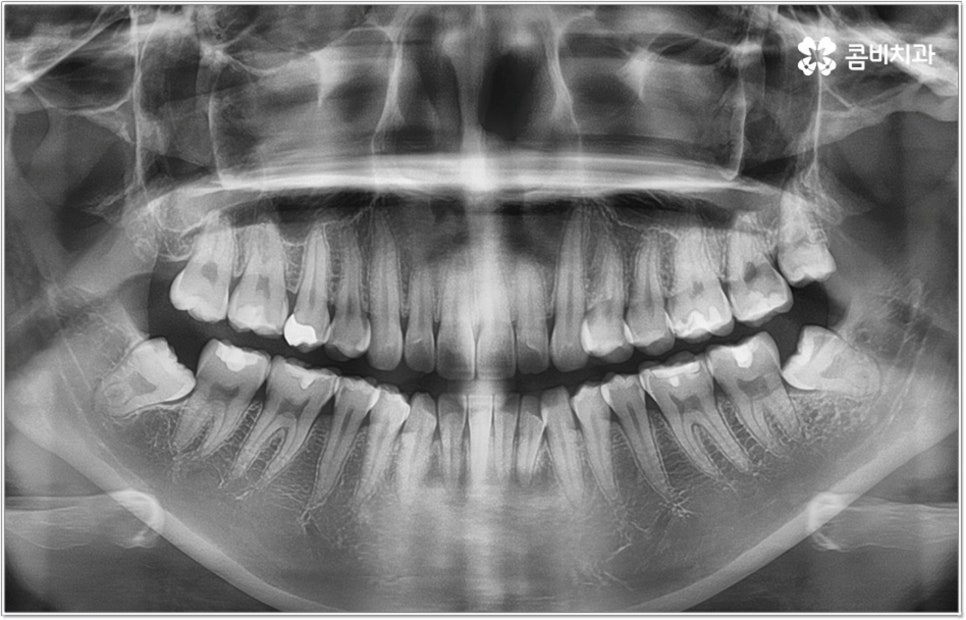

잘 아시다시피 교정이란 치아에 교정 장치 (브라켓) 를 부착하고 와이어에 교정력을 걸어 필요한 방향으로 치아를 이동시킴으로써 고른 치열과 올바른 교합을 가진 정상적인 구강 구조를 회복하는 치과 진료를 의미하는데요, 말씀드린 것처럼 부정교합에는 다양한 형태가 있고 또한 환자분들마다 심각한 정도가 모두 다르기 때문에 현 상태를 면밀하게 체크하고 맞춤 교정 치료 계획을 세우는 것이 무엇보다 중요하다고 할 수 있습니다. 즉 3D CT 와 같은 정밀 진단 장비를 갖추고 있는 치과에서 교정 관련 임상 경험이 풍부한 숙련된 의료진과 함께 치료를 진행하는 것이 필수적이라고 할 수 있어요. 전체 방향 및 세부 플랜을 세울 때 각 환자에 맞게 치아의 이동 속도에 무리가 가지 않도록 하기 위해서 연령이나 발달 상황, 진행 상황을 면밀하게 살펴보는 것이 필요하며 또한 구강 내 공간 유무 및 부정교합 정도에 따라 발치 또는 비발치치아교정 여부를 결정하게 될 거예요.

만약 치아가 이동할 범위를 계산해 봤을 때 공간이 충분하다면 굳이 치아를 뽑지 않고 비발치치아교정 과정으로 치료할 수 있어요. 제일 뒤에 있는 어금니를 더 후방으로 이동시키거나 치간 삭제, 악궁확장장치 등으로 치아 사이를 벌려서 이동 공간을 확보할 수 있으면 비발치치아교정 이 가능한 거예요. 이 때 부정교합이 심각하거나 악골이 치아에 비해 많이 작은 경우, 구조적인 원인을 개선할 필요성이 있는 경우 등 발치 교정을 하는 것이 꼭 필요한 케이스라면 치아를 뽑아주어야 하며, 환자분들의 상황에 따라 다르지만 보통은 소구치를 발치하는 경우가 많이 있습니다.